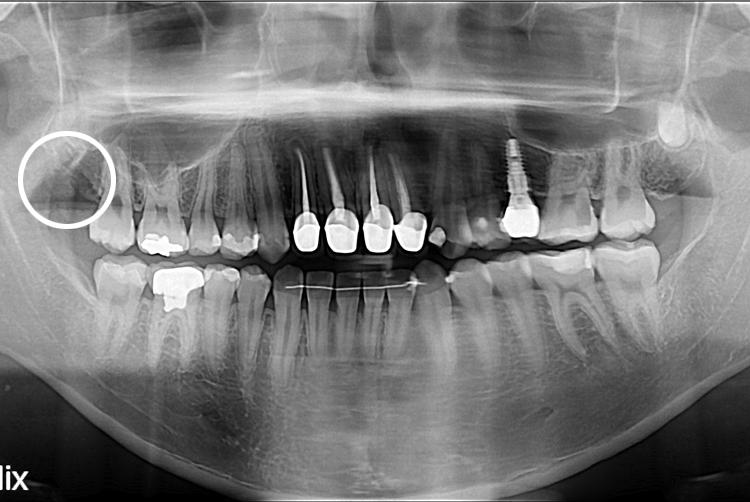

[사랑니] 단순매복 사랑니 발치

치료전 : 2021-03-02

세종치과는 구강악안면외과학 박사이신 원장님이 발치하는 치과 입니다.